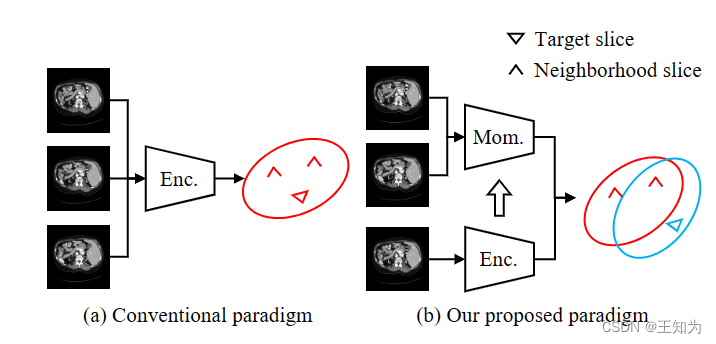

图4. 2.5D基分割模型的传统特征提取范式与我们提出的范式之间的比较。 (a) 传统方法使用一个编码器对所有输入切片进行编码。因此,目标切片和邻近切片的分布是相同的。 (b) 我们提出的范式采用两个编码器分别处理目标和邻近切片。在邻近切片编码器中使用了动量更新。因此,目标和邻近切片的分布是可区分的并且一致的。 (Enc.: 编码器; Mom.: 动量编码器)